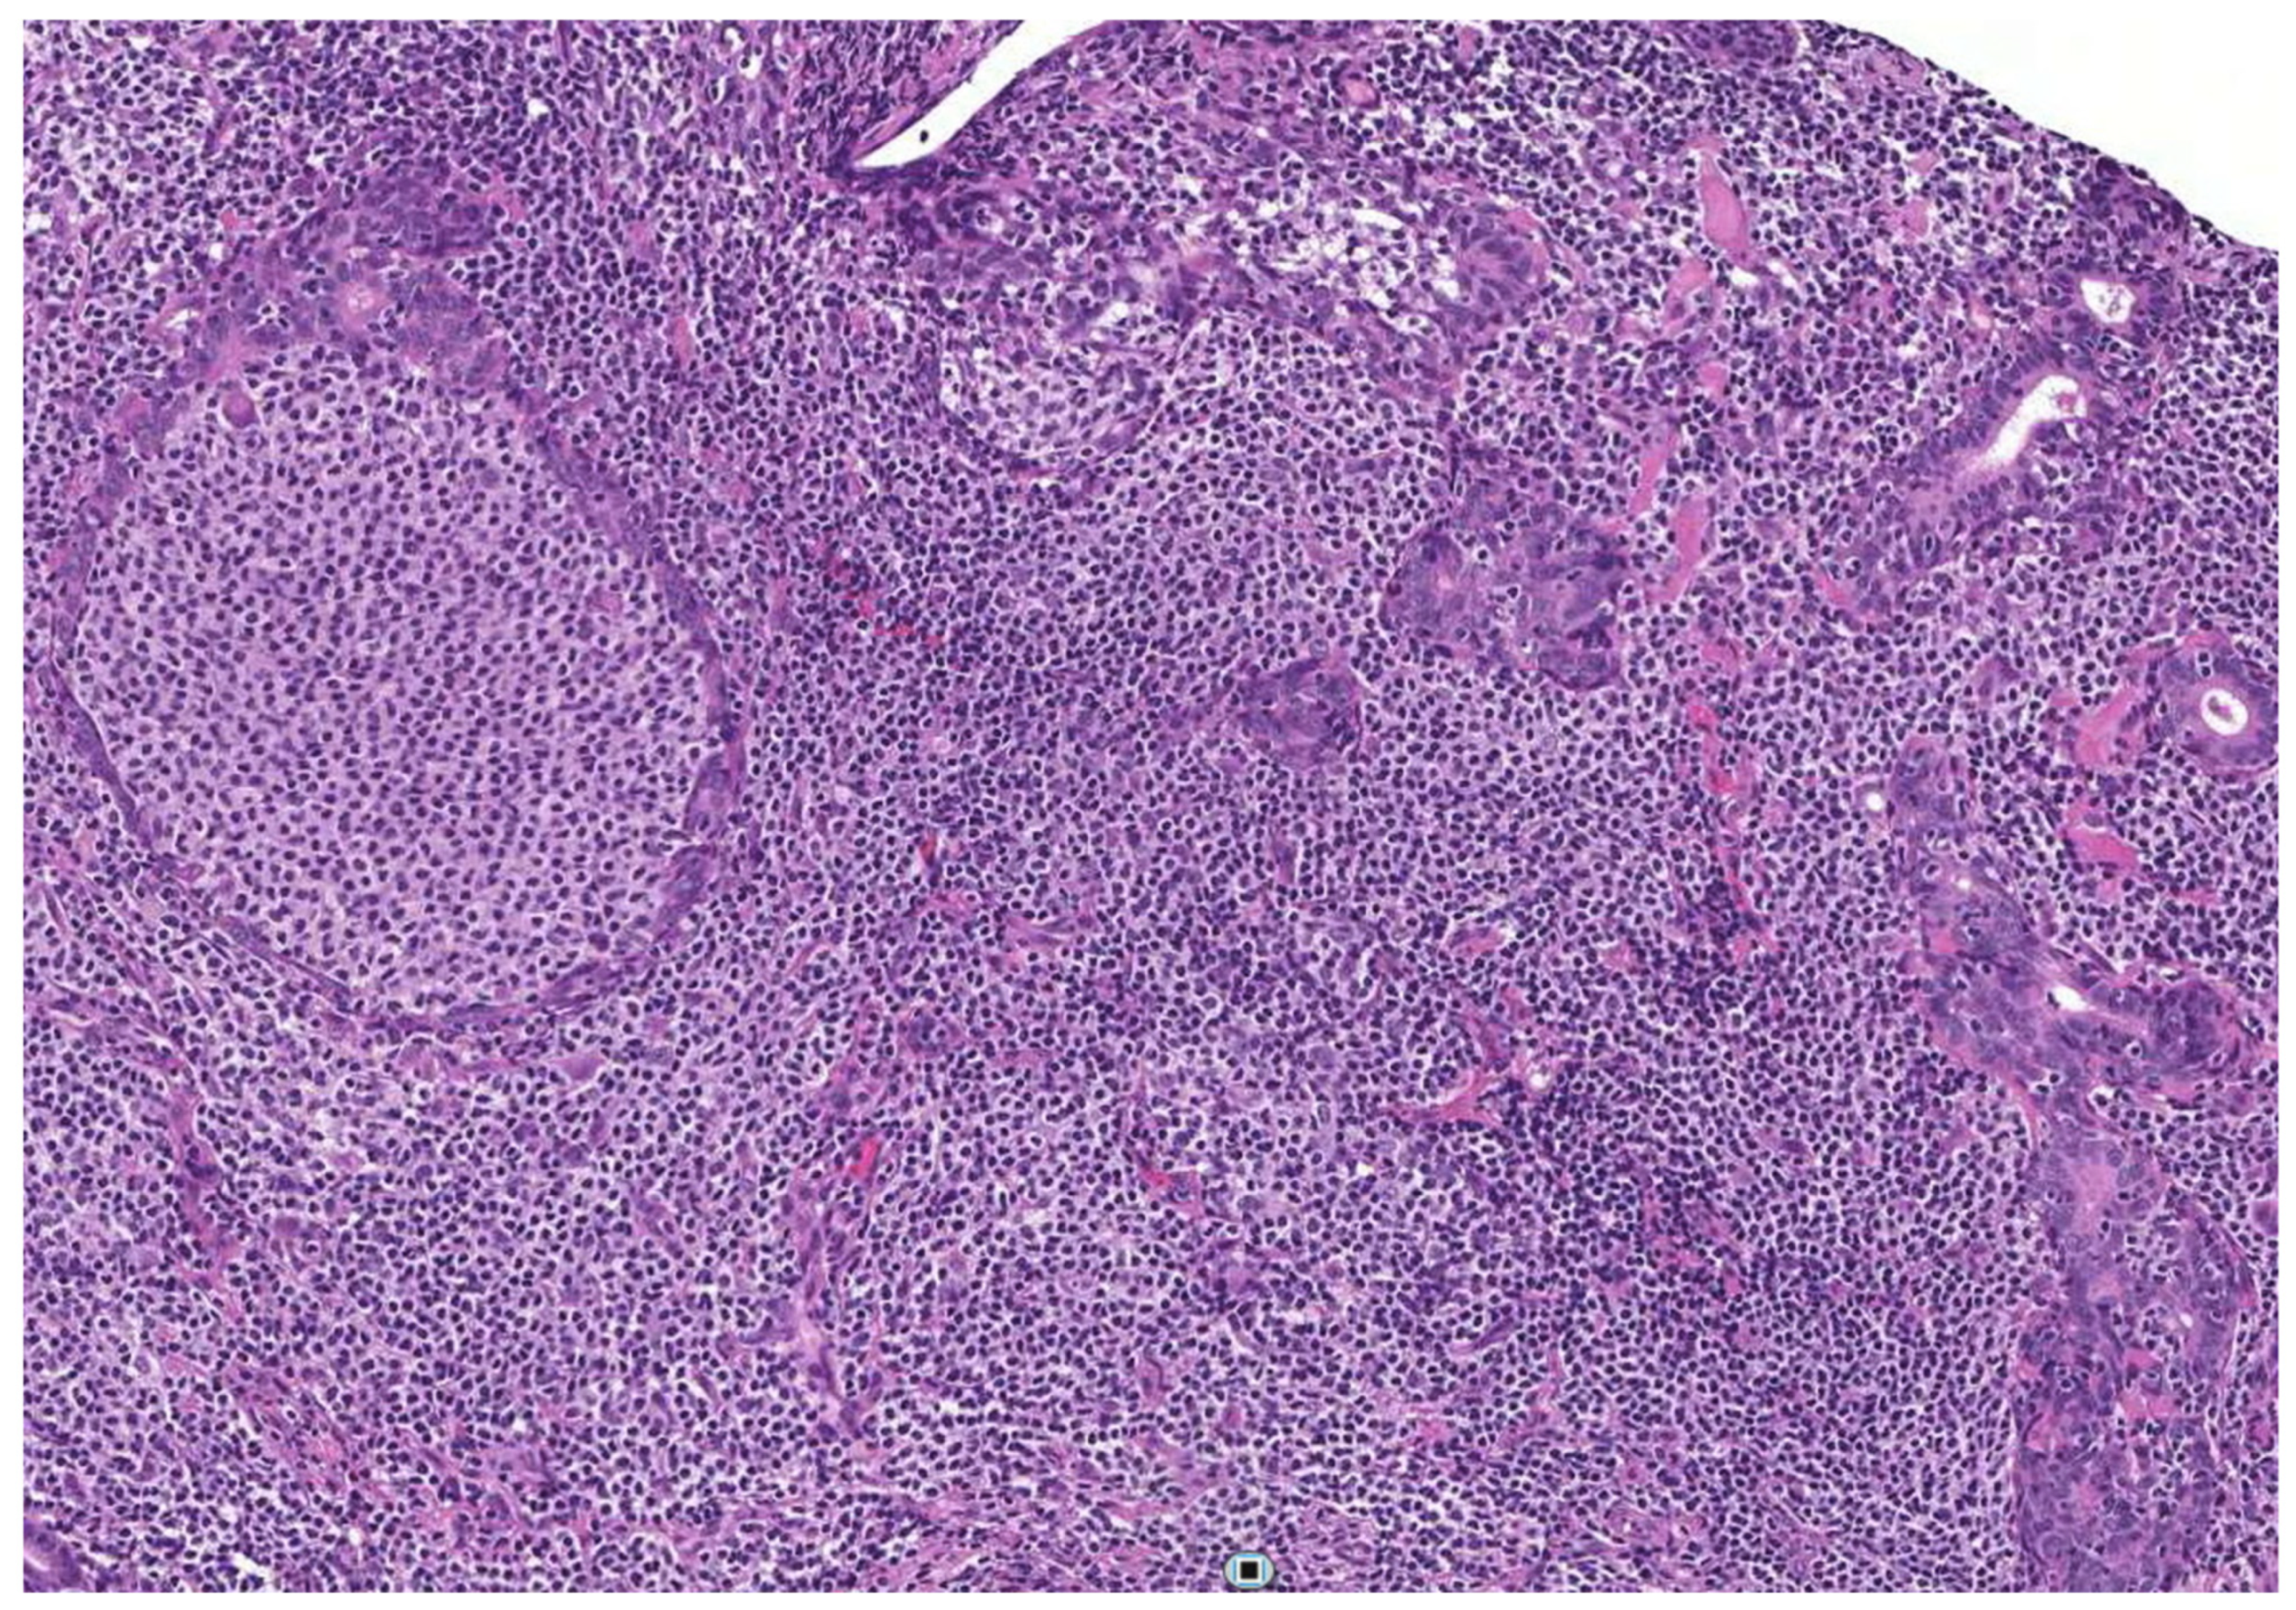

- Zabotti, A.; Zandonella Callegher, S.; Lorenzon, M.; Pegolo, E.; A Scott, C.; Tel, A.; Giovannini, I.; Robiony, M.; Di Loreto, C.; Zuiani, C.; et al. Ultrasound-guided core needle biopsy compared with open biopsy: A new diagnostic approach to salivary gland enlargement in Sjögren’s syndrome? Rheumatology 2021, 60, 1282–1290. [Google Scholar] [CrossRef]

- Kroese, F.G.M.; Haacke, E.A.; Bombardieri, M. The role of salivary gland histopathology in primary Sjögren’s syndrome: Promises and pitfalls. Clin. Exp. Rheumatol. 2018, 36, 222–233. [Google Scholar]

- Barone, F.; Campos, J.; Bowman, S.; Fisher, B.A. The value of histopathological examination of salivary gland biopsies in diagnosis, prognosis and treatment of Sjögren’s Syndrome. Swiss Med. Wkly. 2015, 145. [Google Scholar] [CrossRef]

- Carubbi, F.; Alunno, A.; Gerli, R.; Giacomelli, R. Histopathology of salivary glands. Reumatismo 2018, 70, 146–154. [Google Scholar] [CrossRef]